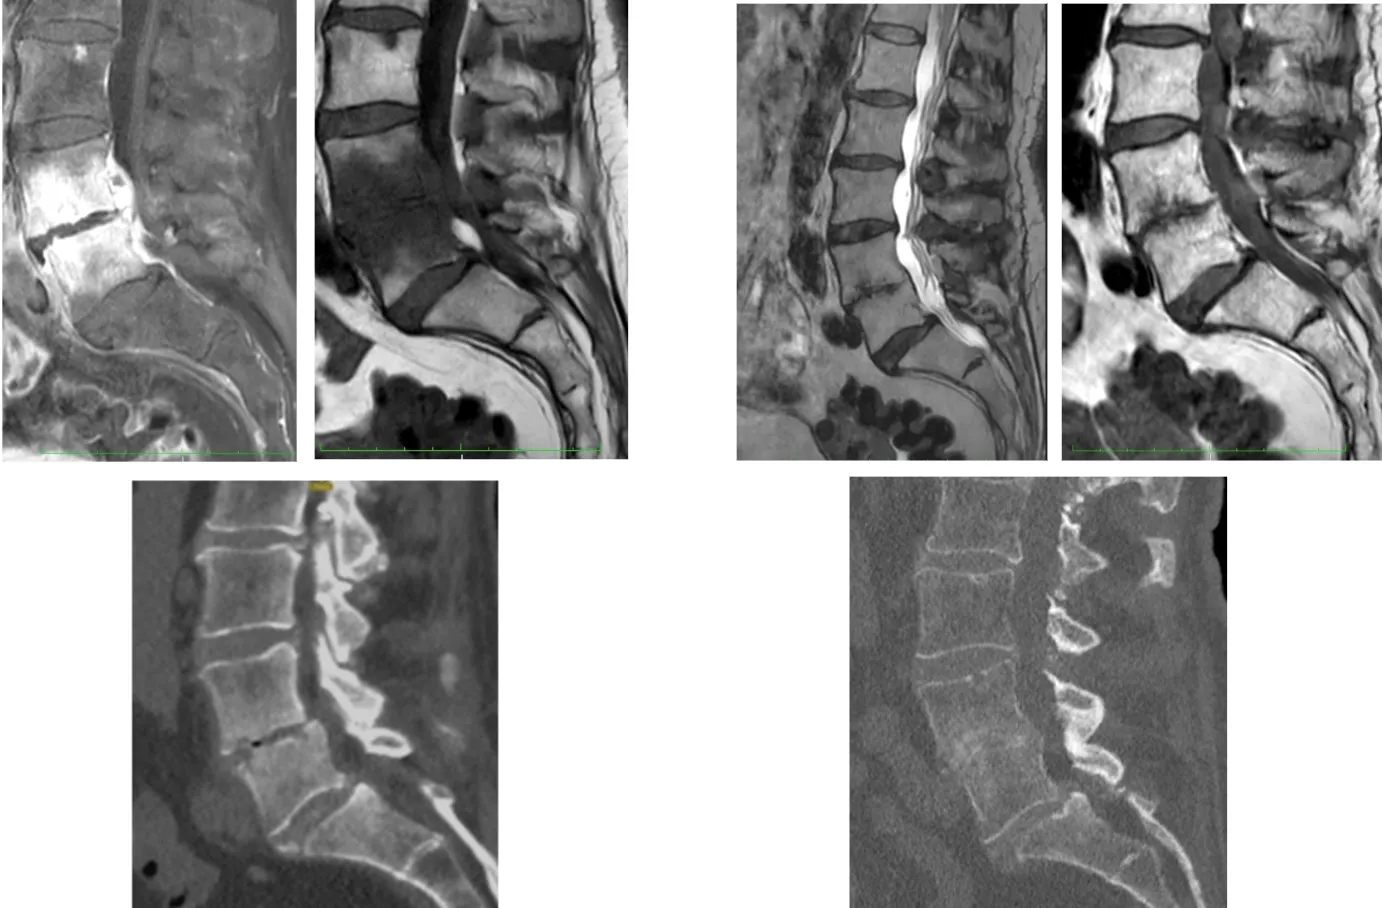

Radiografía simple

Las alteraciones en la radiografía convencional tardan entre 2 y 8 semanas en hacerse evidentes. Permite controlar la evolución de la cifosis y el colapso vertebral, pero tiene una sensibilidad limitada del 73% y una especificidad del 57%.

Tomografía computarizada (TAC)

El TAC es superior a la radiografía para visualizar el disco intervertebral, los cuerpos vertebrales y el grado de destrucción ósea. Es especialmente útil para guiar biopsias percutáneas y valorar los estadios de fusión vertebral. Sin embargo, su sensibilidad (67%) y especificidad (54%) son limitadas para el diagnóstico inicial.

Resonancia magnética (RM)

Constituye la prueba de imagen de elección para el diagnóstico y seguimiento de la espondilodiscitis. La RM presenta una sensibilidad y especificidad superior al 90%, permitiendo una visualización óptima del disco, los cuerpos vertebrales, los abscesos epidurales y la afectación de partes blandas paravertebrales.

La comparación de las diferentes pruebas diagnósticas muestra claramente la superioridad de la resonancia magnética:

| Sensibilidad | Especificidad | |

|---|---|---|

| Rx | 73% | 57% |

| TAC | 67% | 54% |

| RM | > 90% | > 90% |

| PCR | 84% | 71% |